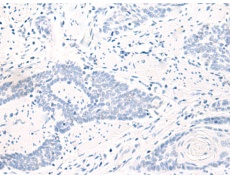

IHC positive control: |

Human esophagus cancer |

IHC Recommend dilution: |

50-300 |